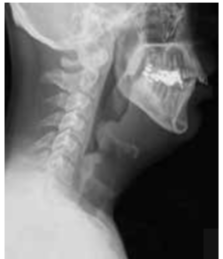

Thumb sign seen in